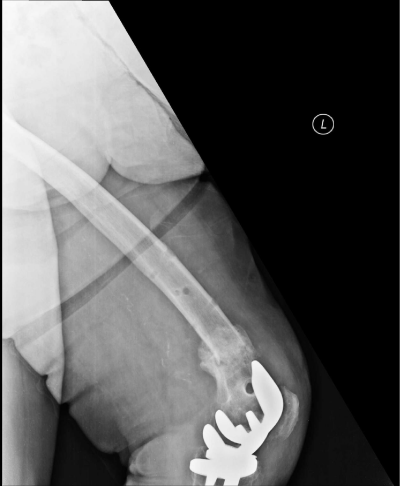

Radiographs demonstrated a fracture at the supracondylar region of the femur with significant displacement and well-functioning prosthesis (Figures 1 and 2). According to Rorabeck classification this fracture was classified as type two.8 Internal fixation was planned, however, due to multiple co-morbidities and relatively high risk of anaesthesia, a decision was made to manage the fracture by external fixation.

Figure 1: The preoperative AP (1) and lateral (2) x-rays of the patient demonstrating a Rorabeck type 2 supracondylar displaced periprosthetic fracture

Figure 2: X-rays of the patient demonstrating a Rorabeck type 2 supracondylar displaced periprosthetic fracture